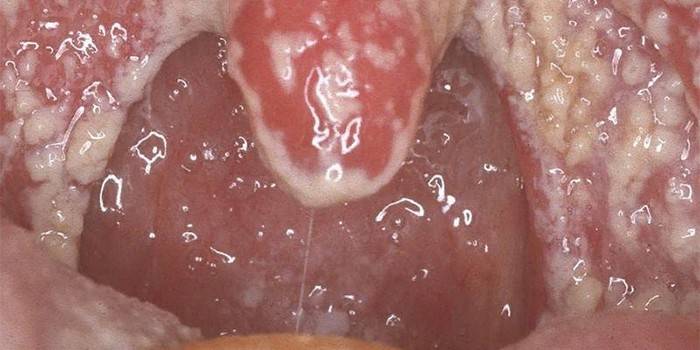

Kandidózu v ústach nemožno prehliadnuť. Huby spôsobujú pre človeka veľa nepríjemností: sliznice ústnej dutiny sú suché, opuchy, vredy a zväčšujú sa jazyk. V dôsledku narušenia mikroflóry sa huba Candida prejavuje týmito príznakmi:

- sčervenanie sliznice;

- bolestivosť, citlivosť;

- pálenie a svrbenie pri prehĺtaní;

- hrudka v hrdle;

- tvarohový povlak;

- prítomnosť bielych bodiek.

Hneď ako sa plesne aktivujú, začnú sa množiť a prenikajú do zdravých buniek. Počas tohto procesu sa tvoria voľne spojené bunkové zlúčeniny nazývané pseudomycelia. Dráždia sliznicu a ničia susediace tkanivá. Kandidóza ústnej dutiny začína zápalom ďasien, objavením sa vredov v ústnej dutine a rohoch pier. Iné príznaky choroby:

- objavia sa belavé plaky, ktoré ovplyvňujú líca, mandle, ďasná;

- ústna dutina je potiahnutá vrstvou mlieka;

- biele vločky a vločky ovplyvňujú pery;

- pri otrave tela toxínmi húb sa pozorujú alergické prejavy.

Na základe počiatočného vyšetrenia bude lekár schopný určiť huby v ústach. Diagnóza nie je náročná, pretože voľným okom je viditeľný biely povlak na jazyku, ďasnách a poschodí. V závažných prípadoch získa hlien v ústnej dutine tmavý odtieň. Pri pokuse o odstránenie povlaku sa pod ňou nachádza začervenaná sliznica, ktorá niekedy krváca. Bakteriologické vyšetrenie náteru pomôže potvrdiť diagnózu. Ak existuje podozrenie na kandidózu pažeráka alebo komplikovanej plesne v ústach, môže odborník predpísať dodatočnú endoskopiu a röntgenové žiarenie kontrastným prostriedkom.